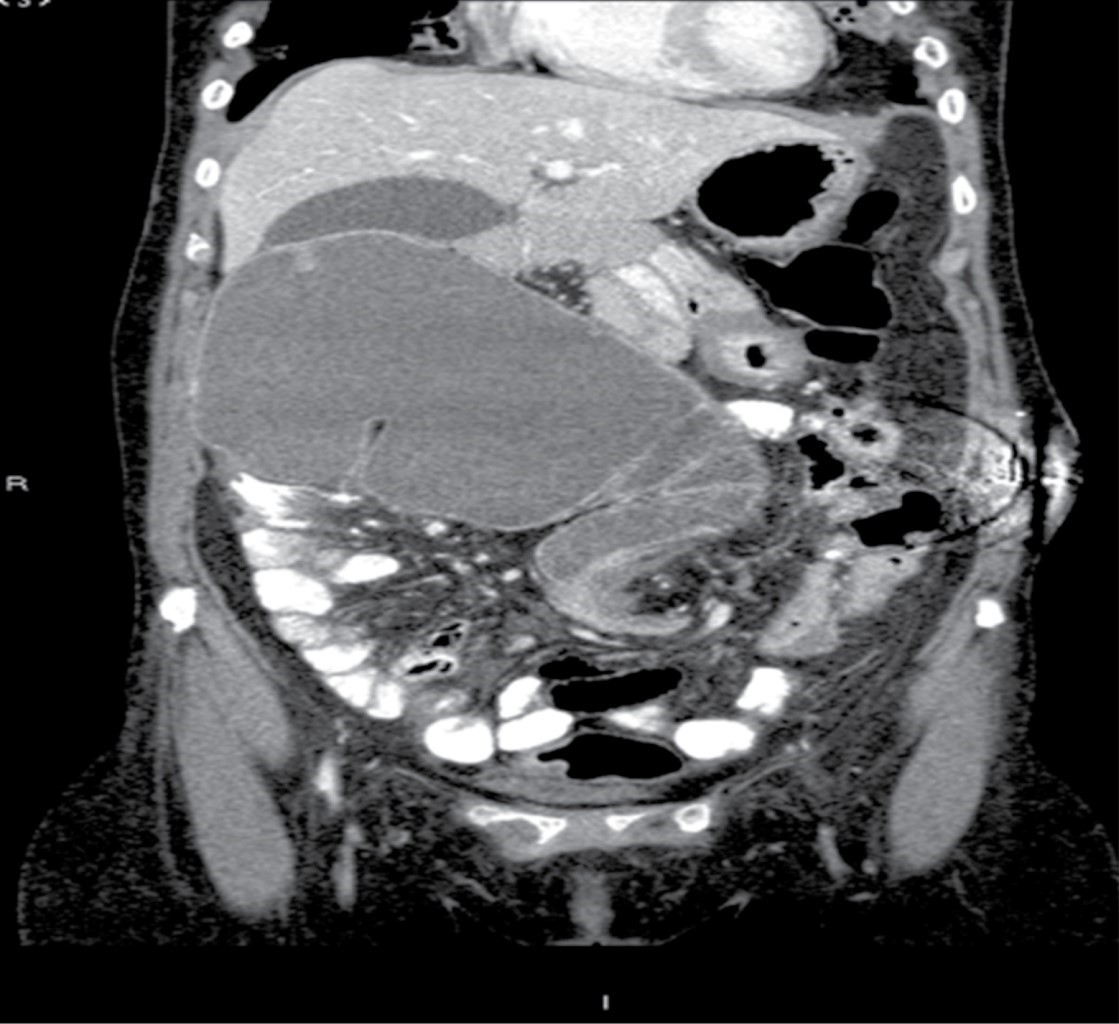

Se solicitaron estudios de laboratorio, los cuales reportaron 12,000 leucocitos por milímetro cúbico, siete bandas y niveles de lactato sérico de 2.8 mmol/l. Posteriormente se realizó una tomografía de abdomen con doble contraste, encontrando importante dilatación cecal, dilatación de colon ascendente y de la porción proximal de colon transverso, junto con una zona de transición hacia tercio distal, localizado en fosa iliaca izquierda. De igual manera, se encuentra hernia de pared abdominal supraumbilical en línea media con escaso tejido graso y epiplón (Figuras 1, 2, 3 y 4).

Figura 4